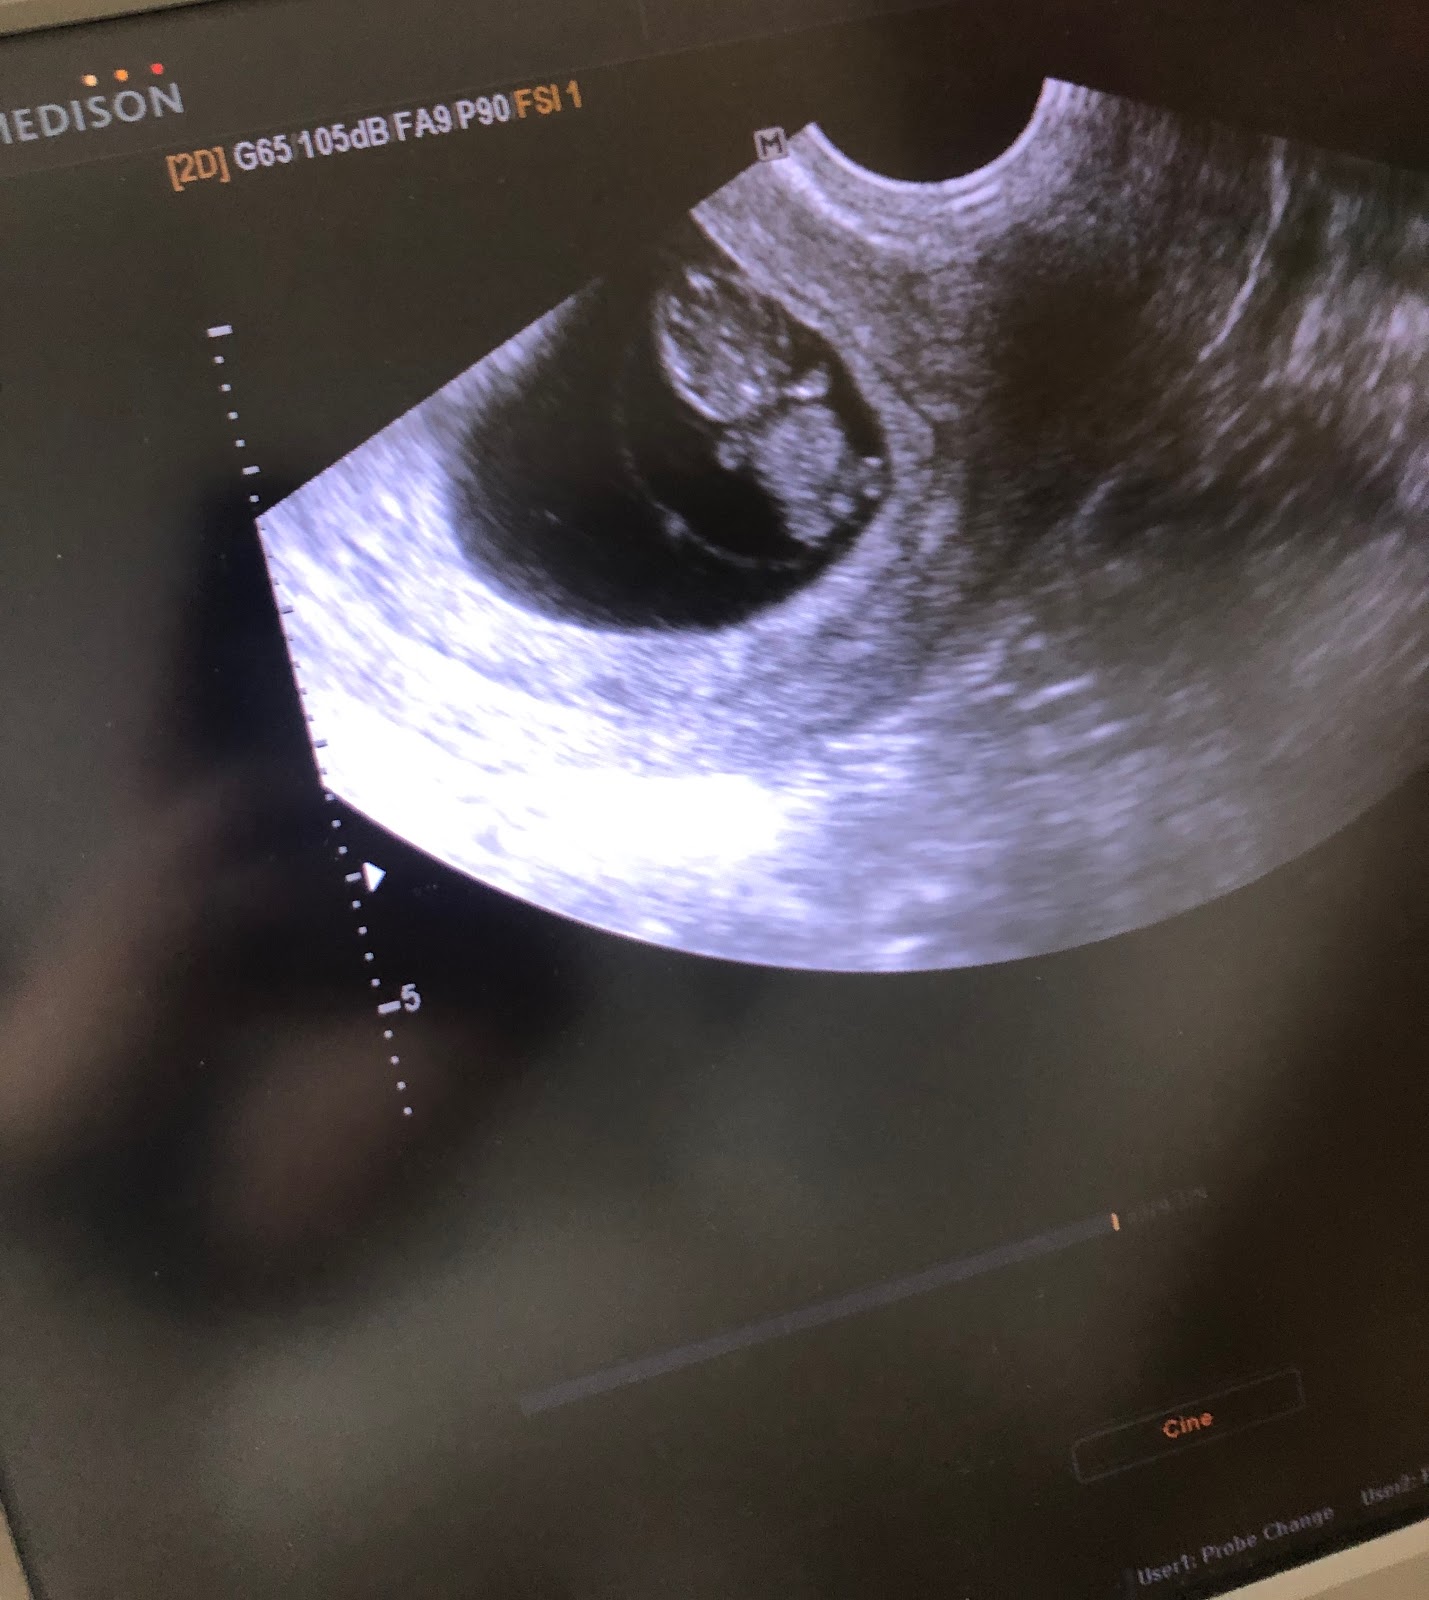

Objednala som sa k lekárovi kam som šla 15.4 a ten mi potvrdil, že čakáme bábätko. Keď som videla tú malú škvrnku s bijúcim srdiečkom doľahlo na mňa úplne šťastie obrovská radosť a mala som čo robiť aby som sa nerozplakala. A potom to prišlo.

Od prvej návštevy lekára som tam bola do tejto doby 2x z toho raz už na poradni, kde mi teda brali 4 ampulky krvi čo mne našťastie žiadny problém nerobí a samozrejme klasický ultrazvuk aby sme zistili teda, koľko meria bábätko a naposledy to bolo 5,6cm.